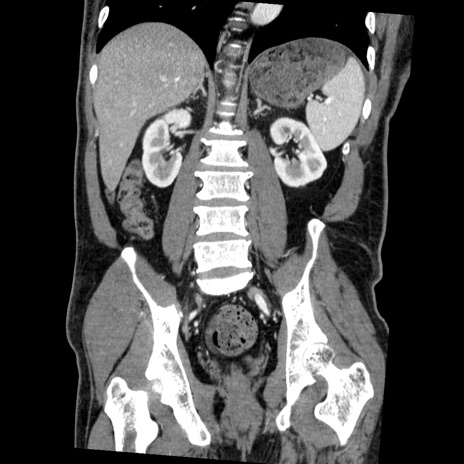

症例22(冠状断像)

【症例】50歳代男性

【主訴】腹痛

【現病歴】AVMからの被殻出血のため回復期リハ病棟入院中。 本日午後3時頃急に下腹部痛が出現した。

【既往歴】AVM、被殻出血、虫垂炎、高血圧

【身体所見】意識晴明、左半身不全麻痺、会話の理解は良好、36.5°C、腹部:膨隆、全体に板状硬、下腹部正中に圧痛点あり、反跳痛-、筋性防御不明、右下腹部にope scar

【データ】WBC 9400、CRP 0.06